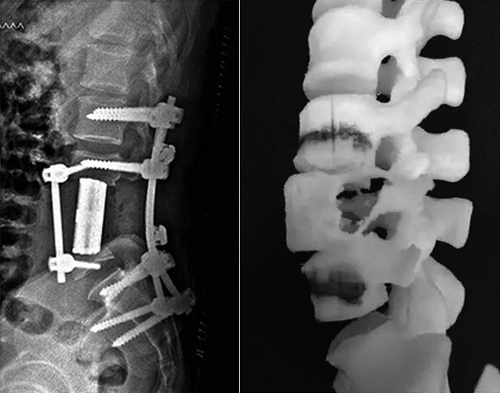

脊椎少一段,南医三院用3D打印脊骨接上了

近日,南方医科大学第三附属医院成功为一名脊索瘤患者切除脊椎上肿瘤,缺损的脊柱用3D打印的人工椎体置换。

3D假体设计 3D打印换脊骨图片

3D ACT人工椎体系统弥补了传统钛网类产品的应用不足,在骨与植入物的融合、避免椎体终板塌陷、组织结构重建等方面具有显著优势,更加符合人体力学和生理结构,术后骨愈合能力佳,发生并发症的几率大大降低。